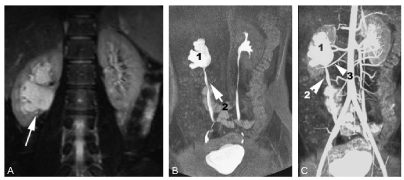

L’uro-IRM permet de réaliser une étude anatomique et fonctionnelle des reins (figure 108.2). La découverte d’un syndrome de jonction chez le grand enfant doit faire rechercher l’existence d’une artère polaire inférieure responsable de l’obstacle.

Fig. 108.2 Syndrome de la jonction pyélo-urétérale en uro-IRM : coupe coronale pondérée T2, puis images réalisées après injection de gadolinium.

En T2 (A), il existe une dilatation du pelvis rénal droit (flèche). Sur l’image « urographique » (B), le pelvis rénal (1) est dilaté, contrastant avec l’uretère de calibre normal (2). L’image (C) correspond à la superposition du temps angiographique et du temps urographique ; le pelvis rénal dilaté (1) et l’uretère normal (2) sont retrouvés ; il existe une artère polaire inférieure (3) qui croise la jonction pyélo-urétérale et qui est responsable de l’obstacle.

Source : CERF, CNEBMN, 2022.